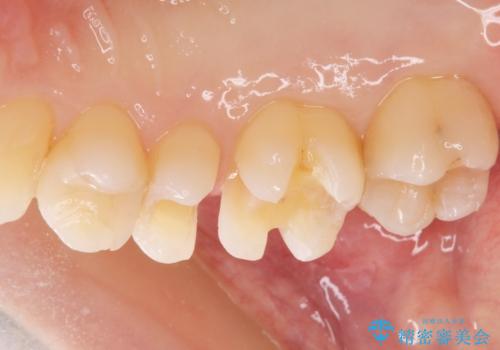

セラミックの詰め物は歯質とピッタリ適合して虫歯の再発率が低いです。

白い詰め物が入り大変満足して頂けました。